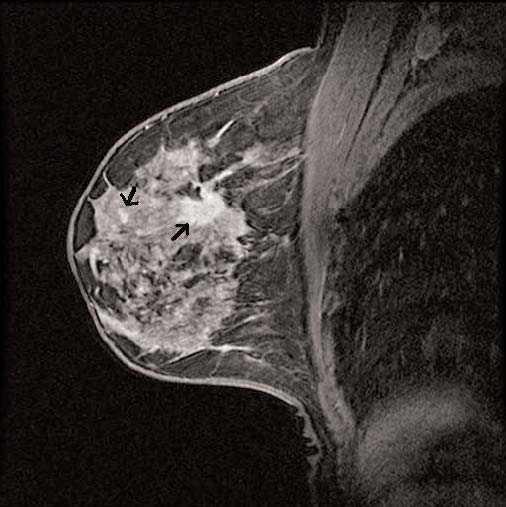

Con la RM mamaria preoperatoria, además de delimitar con mayor exactitud la extensión del tumor, tratamos de buscar lesiones multifocales, multicéntricas o en la mama contralateral que no se hubiesen visto en el estudio mamográfico y ecográfico previos. Se define como lesiones multifocales aquellas separadas de la lesión principal menos de 4 cm y situadas en el mismo cuadrante (fig. 1); como multicéntricas aquellas lesiones situadas en diferentes cuadrantes del de la lesión principal o separadas más de 4 cm (fig. 2), y como bilaterales aquellas lesiones que aparecen en la mama contralateral a la lesión principal.

Figura 2. Imagen de carcinoma multicéntrico.